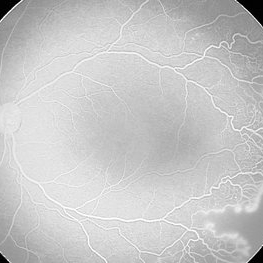

Angiogram taken on a 42 weeks corrected age baby born at 34 weeks. The baby developed lung disease and received oxygen 100% for 4 weeks.

Photographer: Maria A. Martinez-Castellanos. Asociacion para Evitar la Ceguera en Mexico

Imaging device: RetCam II

Condition/keywords: retinopathy of prematurity (ROP)